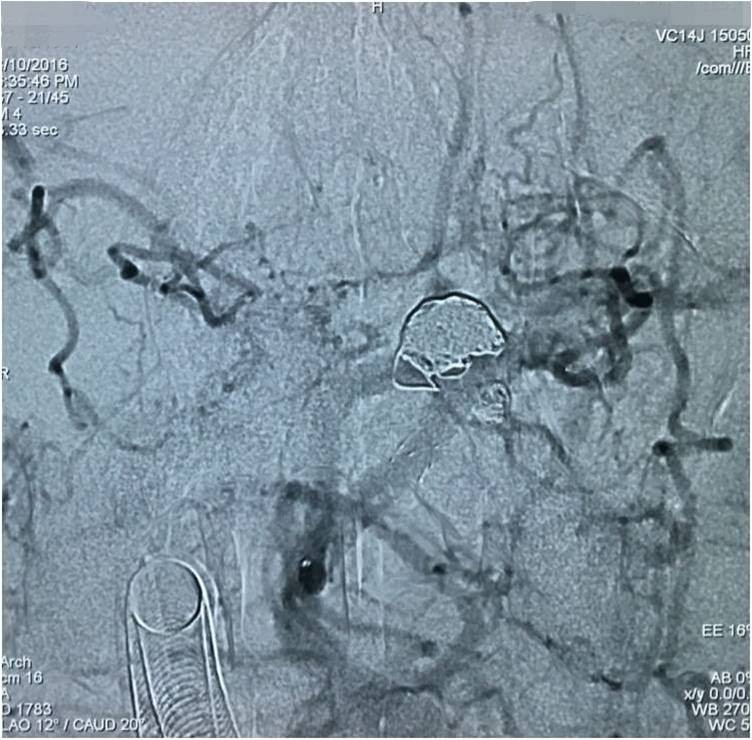

下面是术后各个角度的左椎动脉造影,可见基底动脉顶端动脉瘤和左小脑上动脉瘤完全栓塞,载瘤动脉畅通。基底动脉顶端动脉瘤的子瘤终于被消灭。

▼术后左椎动脉造影正位反汤28度。

▼纯正位。

▼侧位。

▼正位汤46度。